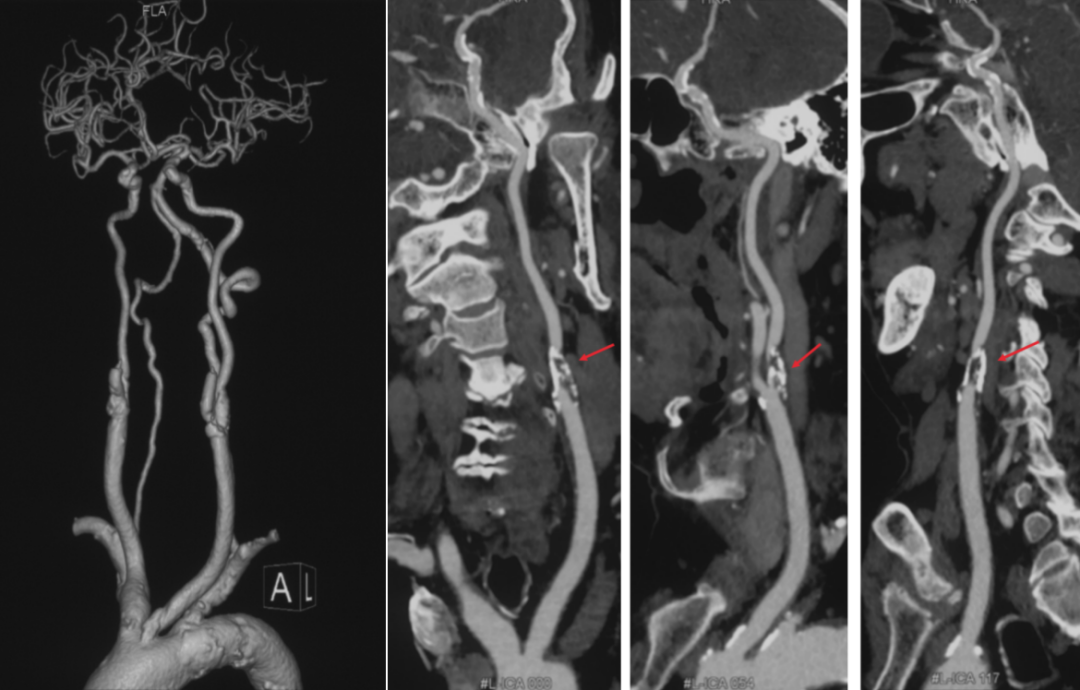

术前头颈CTA提示左侧颈总动脉(L-CCA)的狭窄处钙化严重,且L-CCA和主动脉弓的夹角很锐(图1),显然,这样的颈动脉狭窄更适合剥脱(CEA)。但由于患者高龄,且20天前经历过心梗,存在全麻手术禁忌,因而安排了CAS。

图1. 术前CTA。

多数情况下,经桡并不是CAS的优选通路,但对于某些特殊情况下,经桡确实更好,例如牛角弓和主动脉弓先天闭锁。高老师在2020年的一期宣武CRC星期五详细讨论过这个问题,推荐感兴趣的同道点击阅读别无他途:当颈动脉支架遇到主动脉闭锁,左桡入路来帮忙!。对于这个患者,经右桡做,导引导管的“拐角”似乎差不多(图6)。

图6. 经桡入路(黄色)和经股入路(红色)的路径比较。